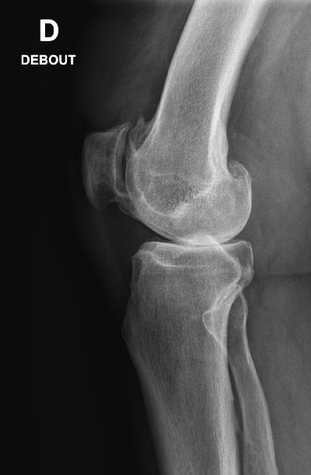

Genou